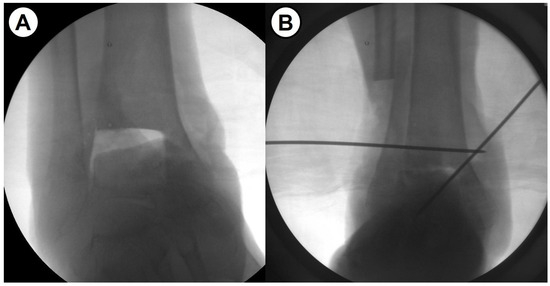

Figure 1.

(A,B) Intraoperative fluoroscopic images show the effects of the fibular osteotomy on ankle fusion.

As one of the solutions for severe bone defect in ankle fusion, fibular osteotomy allows for upward movement of the talus, minimizing the gap and the amount of bone grafting needed, maximizing the contact surface, and optimizing contact area through the correction of coronal plane deformity (Figure 1). We hypothesized that shortening ankle arthrodesis using fibular osteotomy and anterior fusion plate would provide advanced mechanical stability as well as excellent fusion rate. In addition, leg length discrepancy (LLD), which is concerned to be a main drawback of this surgical technique, may demonstrate minimal clinical effects. Given this background, this study aimed to evaluate the intermediate-term clinical outcomes after a novel shortening arthrodesis using fibular osteotomy for ankle arthropathy with severe bone defect.